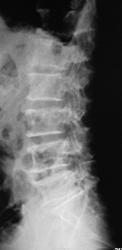

Пациент направлен на рентгенографию костей таза и поясничного отдела позвоночника.

На фоне ввраженной пневматизации кишечника явные деструктивные изменения в костях таза. В отношении позвонков уверенности меньше: корни дужек сохранены, отдифференцировать газ от деструктивных очагов на данных снимках не берусь. На 1-е место поставила бы миеломную болезнь (кстати, что в анализе крови?), на 2-е метастатический процесс. ("-озы" не беру во внимание).

Mts в кости смешанного характера,(очень часто такие изменения дает prostatae)

Рак предстательной железы.